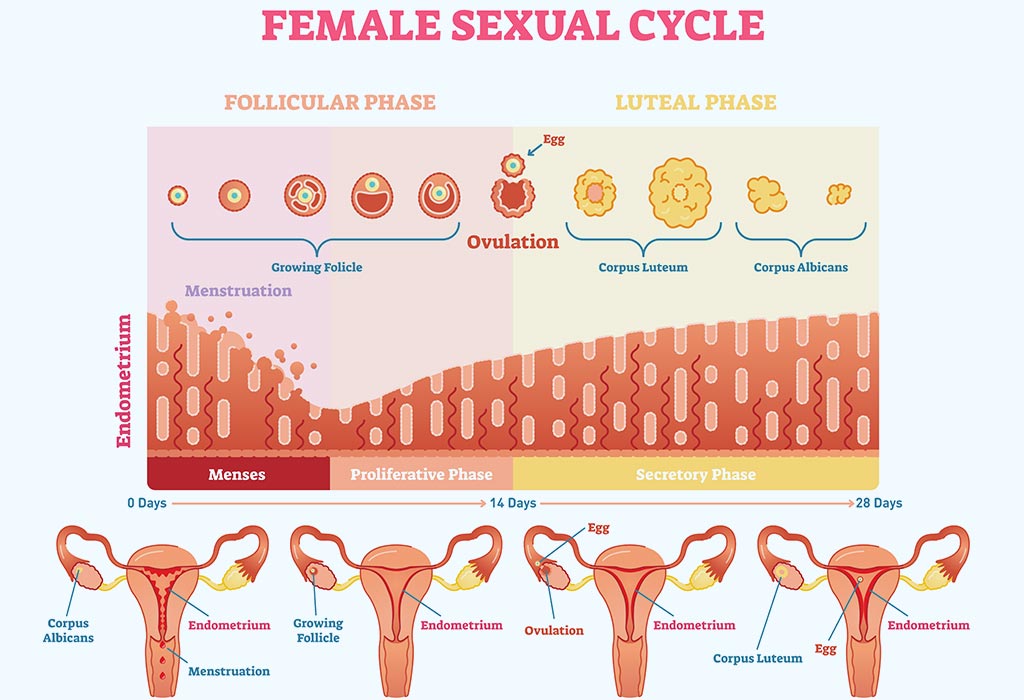

Endometrial Thickness Whats The Normal Range For Conceiving .

Endometrial Thickness What Is The Normal Range .

Endometrial Thickness Whats The Normal Range For Conceiving .

Endometrial Thickness Whats The Normal Range For Conceiving .

The Endometrial Cycle Glowm .

The Endometrial Cycle Glowm .

Gcse Science Hormones Wikibooks Open Books For An Open World .

Endometrial Thickness Whats The Normal Range For Conceiving .